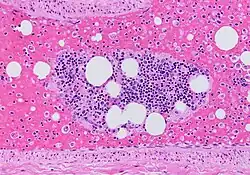

Histopathology of a pulmonary artery from autopsy. It shows a fat embolism (seen as multiple empty globular spaces on this H&E stain since its processing dissolves fat). There is a bone marrow fragment in the middle, and multiple single hematopoietic cells in the blood, being evidence of fracture as the source of the embolism.